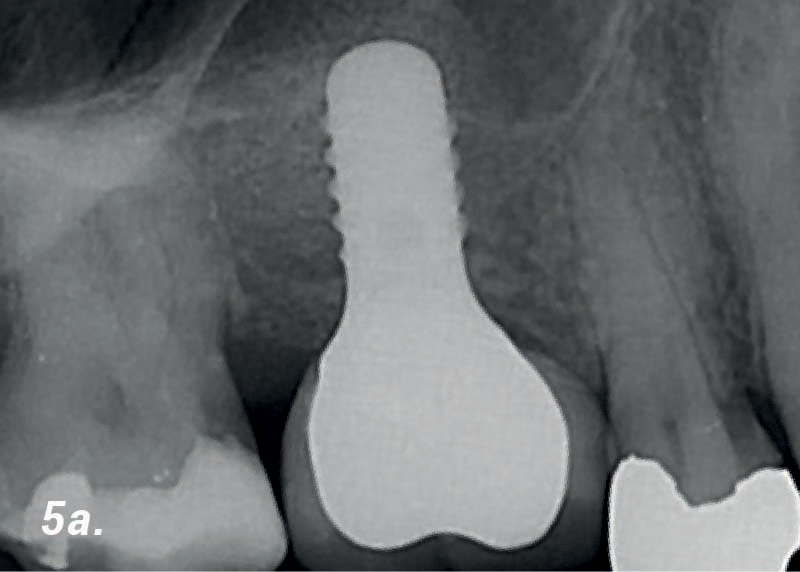

• 5a. Se utilizaron implantes con un ancho de 4 mm. colocados en lugares protésicamente designados.

• 5b. Después de 6 meses: Tomografía volumétrica digital (TVP) muestra suficiente cantidad de hueso recién formado.